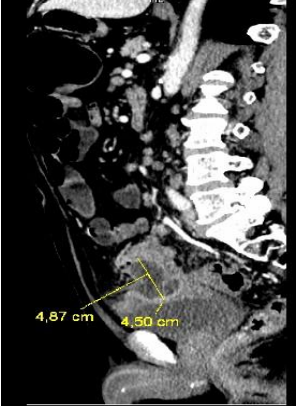

The initial blood analysis revealed a leukocytosis of 15,000/µL (4,000-11,000/µL) with neutrophilia and C-reactive protein (CRP) of 245 mg/L (0-0.5 mg/L), as well as anemia with a profile of chronic disorders. The abdominal x-ray showed abundant gas without signs of intestinal obstruction. An abdominopelvic CT with intravenous contrast was performed (Figure. 1, 2 and 3) in which radiological data compatible with a new episode of diverticulitis were observed, as well as an abscess on the lower surface of the sigmoid.

Figure 3: Sagittal section of abdominopelvic CT, with abscess measuring 4.87 x 4.5 cm